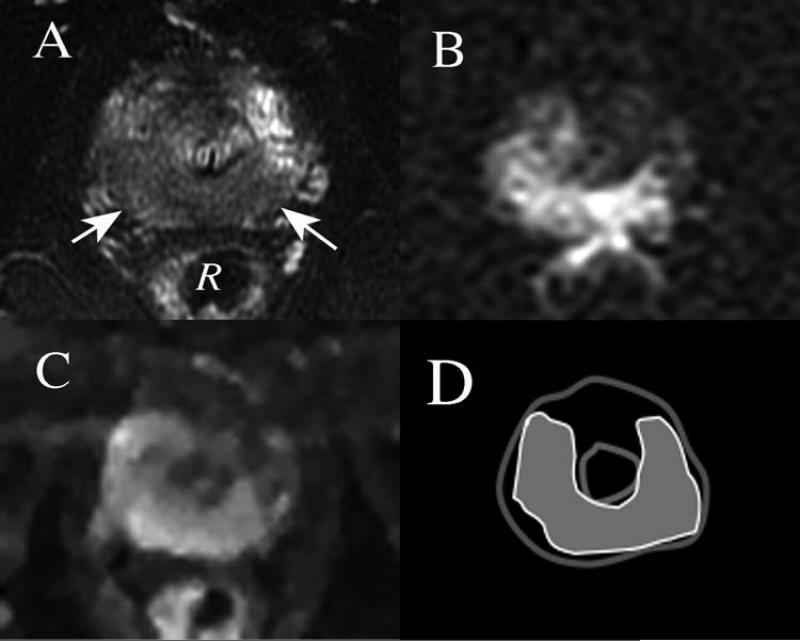

Four MRI methods which have been extensively evaluated are standard T2-weighted imaging (T2W), magnetic resonance spectroscopic imaging (MRSI), diffusion-weighted imaging (DWI) and dynamic contrast enhanced (DCE) imaging. Early studies of T2W indicated that histologic correlation with such images was inaccurate due to a lack of specificity of MRI appearances for cancer24,25. In a more recent large multi-institutional study23 at 1.5 T, ROC analysis was performed to evaluate the performance of T2W and MRSI in localization of the prostate cancer index lesion, and another recent study22 evaluated T2W, DWI and DCE using a similar study design. The AUC values determined in the former study were 0.60 for T2W alone and 0.58 for MRSI interpreted along with the T2W; in the second smaller study, the AUC values for T2W, DCE and DWI respectively were 0.673, 0.592 (mapping the parameter Ktrans from the DCE), and 0.689. Overall, the AUC values indicate rather poor performance for MRI in cancer localization, although the newer technique of DWI appears promising. In spite of these findings, it is likely that further improvements in the techniques for creating MR images, and higher field strength MR systems with greater SNR, will lead to better performance in the future. An example of imaging of prostate cancer in vivo with newer techniques, and at higher field strength, 3 Tesla, is shown in Figure 1. The scans are a recent preoperative MRI of a patient prior to radical prostatectomy, along with a diagram showing the location of the index cancer drawn from histopathologic analysis of the prostatectomy specimen. The images are from an ongoing HIPAA-compliant prospective study at our institution with IRB approval. The lesion appears to be identifiable using T2W (Figure 1A), and with advanced techniques of DWI with restricted field of view26 (Figure 1B) and DCE27 (Figure 1C), although the depiction of tumor in the various MR images does not conform perfectly to the pathologic mapping (Figure 1D). More recently developed DWI techniques using high values of the diffusion encoding parameter b28,29 (Figure 1B, in which a high b value of acquisition was used (1600 s/mm2)), have been shown particularly sensitive to the depiction of prostate cancer within the gland. In spite of its limitations, MRI has been proved more accurate than competing techniques such as ultrasound in depicting prostate cancer, and has been used successfully as a method for guiding biopsy for prostate cancer30,31. The suggestion has also been made that a “multiparametric” approach, in which the various forms of MRI are used in combination might be more effective than any single sequence, in localizing the index lesion within the prostate22,32,33, and there are also indications from these and other studies34 that larger tumors with more higher Gleason grade tumor are more readily detectable, and differ more in MRI characteristics, than smaller cancers. Since accurate targeting of cancer index lesions within the gland is required if focal ablative techniques are to be successful, the inconsistent ability of current MRI techniques to depict cancer accurately in the prostate appears likely to limit its utility as a localization tool in many cases. There is considerable promise, however, for improved accuracy of depiction, and perhaps even provision of some insight into tumor grading with MRI at higher field strengths, and using the most advanced techniques available.

Figure 1.

Axial images at level of the prostatic apex obtained in a 3 Tesla scanner, of a patient with biopsy-proved prostate cancer prior to radical prostatectomy. A) T2-weighted image shows large region of decreased signal intensity posteriorly (arrows). R = Rectum. B) Reduced field of view Diffusion weighted image (Rfov DWI) obtained using high b value (b=1600 s/mm2) shows high signal intensity roughly corresponding to the low signal region in the T2-weighted image C) Dynamic contrast enhanced (DCE) image displaying maximal enhancement in early arterial phase also indicates early enhancement of a similar region in the apex of the prostate gland. D) Pathologic map showing the distribution of cancer in gray, found in prostatectomy specimen at this level in the gland.